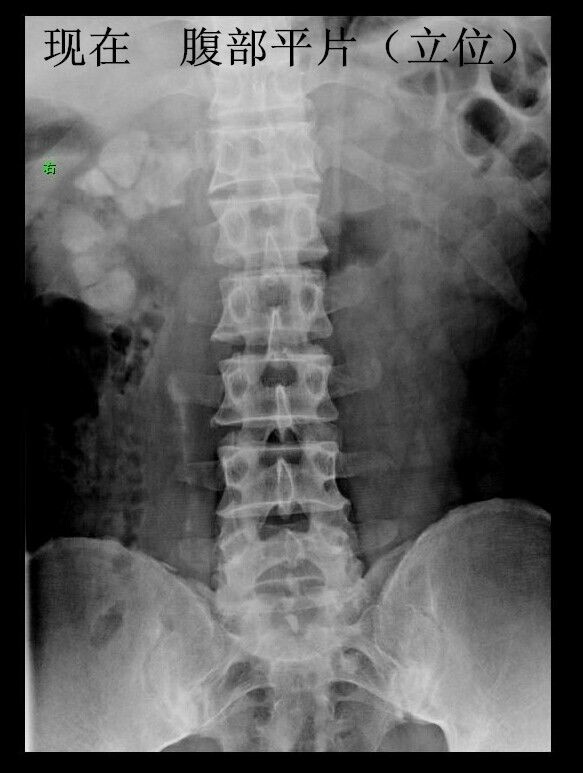

男性青年,未婚。 主诉:咳嗽数月,发现血尿三天。 现病史:患者半年前出现咳嗽症状,自服“消炎药”可减轻,一直未愈,近来加重。右腰背部偶感不适。发现终末血尿三天。患者自述近来消瘦、乏力。精神可,饮食可,睡眠好。 既往史:患者四年前因粟粒性肺结核就诊于当地结核病医院,给予口服抗结核治药物治疗(具体药物不详),后复查未见明显异常。 个人史:吸烟十年。 婚育史:未婚。 家族史:父母体健,无遗传病史。 实验室检查:肌酐:200umol/L(59-104) 尿素:10.4umol/L(2.86-8.2) 本院非结核病防治医院,无结核相关实验室检查。其余检查无阳性发现。 影像学检查(见插图): 1.四年前胸部平片及CT显示:双肺密布粟粒样结节,考虑肺结核。 2.现在胸部CT示:右肺尖及双肺背侧可见片状不规则高密度影,右肺中叶见厚壁空洞。考虑空洞型肺结核。 3.现在行腹部立位平片及CT示:右肾呈高密度团块状,结合病史考虑肾自截。 4.为进一步明确分肾功能,行核素肾动态显像示:右肾未见明显血流灌注,右肾未见明显显影,右肾功能重度受损,右肾肾图呈低水平延长线性改变。左肾功能大致正常。 诊疗经过:鉴于右肾无功能,行右肾摘除术(送病理,回报:肾结核)。请胸外科会诊,建议转入胸外科行肺段切除术。目前右肾摘除术后。 小结:近年来结核病例有上升趋势,尤其是肺结核。本病例类似的情况较少见,特此分享供大家学习。